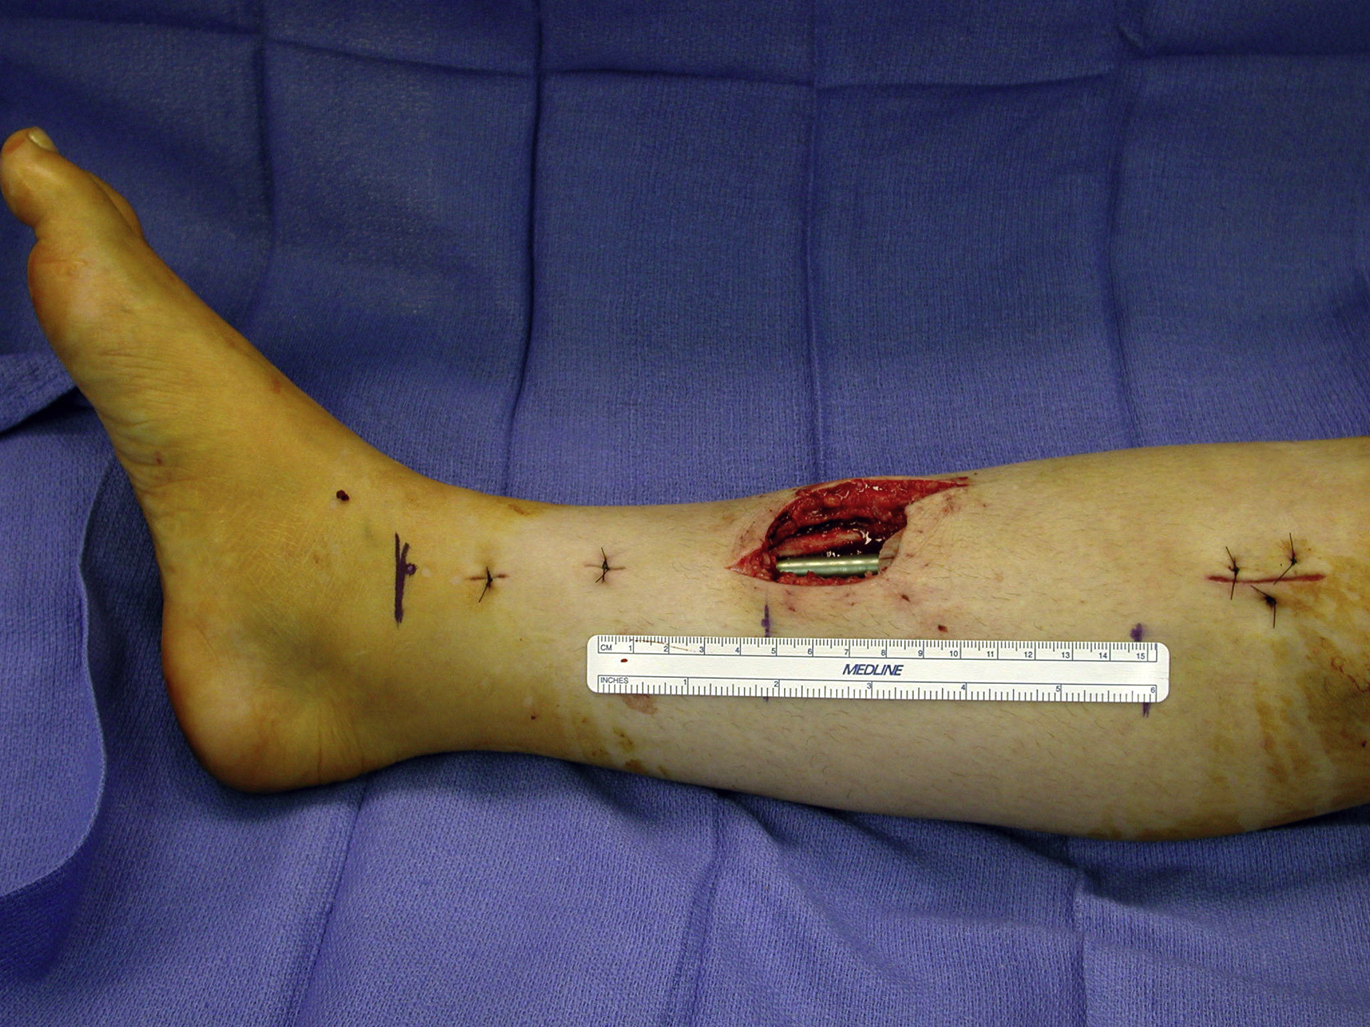

The flap dissection is done under tourniquet control. An existing wound can be extended into the incision both proximally and distally. For a proximally based medial hemisoleus muscle flap, once the medial hemisoleus muscle is identified and dissected freely from the medial gastrocnemius muscle, its insertion is divided distally at a level close to the Achilles’ tendon, depending on the length of the flap rotation required. The medial half of the muscle is split longitudinally along with a midline between the bellies of the soleus muscle. To cover a wound in the distal third of the leg ( Fig. 4 ), the proximally based medial hemisoleus muscle flap is elevated only to the level just below the junction between the middle and distal thirds of the leg with an emphasis on the preservation of as many major perforators to the flap as possible, even in the distal-third of the leg, while allowing an adequate arc of flap rotation ( Fig. 5 ). These perforators are critical sources of blood supply to the distal portion of the medial hemisoleus muscle flap and should be preserved whenever possible. During flap dissection, only the muscular portion of the soleus muscle is used as the flap; the tendinous portion of the soleus is left intact ( Fig. 6 ). The spared tendon is then approximated to the remaining lateral half of the soleus muscle with nonabsorbable sutures. This technique may minimize functional loss of the leg after the flap is harvested. With these refined techniques for the flap dissection, the flap can be suitable for a more proximal defect in the distal third of the leg.

This author prefers an intraoperative dissection of the soleus muscle to confirm the level of the distal muscle insertion, although a preoperative MRI can easily identify the location of the soleus musculotendinous junction in the ankle. Once the medial hemisoleus muscle is identified and dissected freely to the level at the junction between the middle and distal thirds of the tibia, the major perforators from the posterior tibial vessels to the medial half of the soleus muscle within even distal third of the tibia should be identified ( Fig. 7 ). Next, the surgeon must be attentive in the preservation of these perforators when designing the adequate arc of flap rotation to cover the target soft tissue defect or exposed hardware ( Fig. 8 ). If needed, the medial hemisoleus muscle can be extended more laterally after longitudinally splitting, so that the flap can be made wide enough to cover a relatively large wound in the distal third of the leg. These modifications made by the author to the surgical techniques in flap dissection emphasize the preservation of an adequate blood supply to the distal portion of the medial hemisoleus muscle flap after flap elevation. These techniques maximize the reliability of the medial hemisoleus muscle flap and expand its role in reconstruction of distal third tibial wounds , , , ( Fig. 9 ).